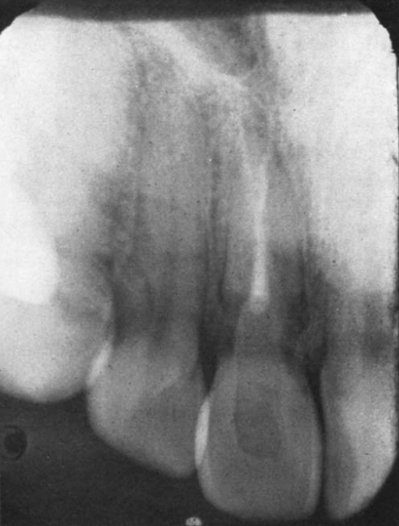

Пациентка вновь обратилась в клинику в январе 1976 года. Примерно за месяц до этого обращения она обратила внимание на небольшую припухлость в области десневого сосочка между левыми центральным и боковыми резцами. В области десневого сосочка был выявлен свищевой ход. Рентгенограмма (рис. 10) показала обширную наружную резорбцию в дистальном отделе корня и незначительную резорбцию в мезиальной области. Пациентка отметила, что в анамнезе у нее не было повторных травм этой области, кроме первоначальной травмы в 1966 году.

Рис. 4. Клинический случай 4. В 1976 году рентгенограмма показала обширную наружную резорбцию в дистальном отделе цервикальной области корня и незначительную резорбцию в мезиальной области.